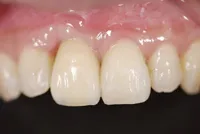

前歯欠損の為来院されたケース

■治療前

■治療後

治療のポイント

- 骨幅が狭い状態です。

- インプラントを埋めると同時に、骨を作る処置をさせて頂きました。

| 主訴 | 上顎の抜歯した箇所の機能障害・審美障害 |

|---|---|

| 治療方法 | 上顎の欠損部位に1本のインプラントを埋入し、同時に外科的治療で骨造成を行った |

| 治療期間 | 約1年 |

| 通院回数等 | 10回 |

| 費用 | 550,000円(税込) |

| リスク・副作用 | 外科的に骨を作る為、治療後に腫れることがある |